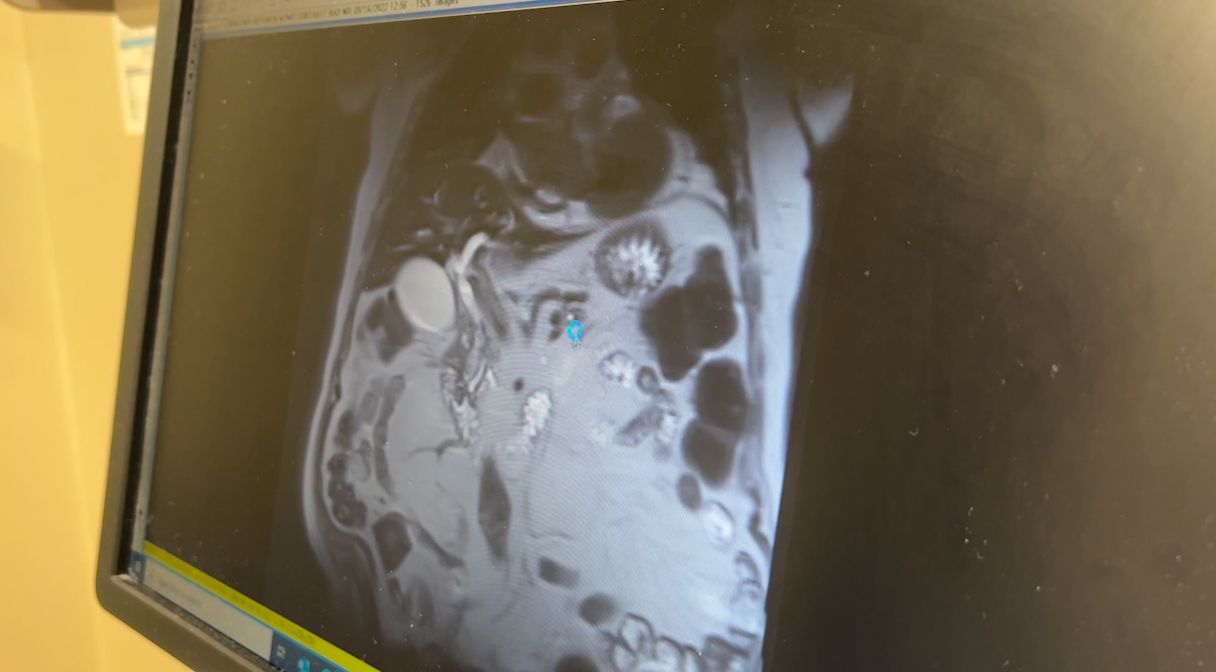

Liver Cancer Causes, Symptoms, Diagnosis, Prognosis and Treatment